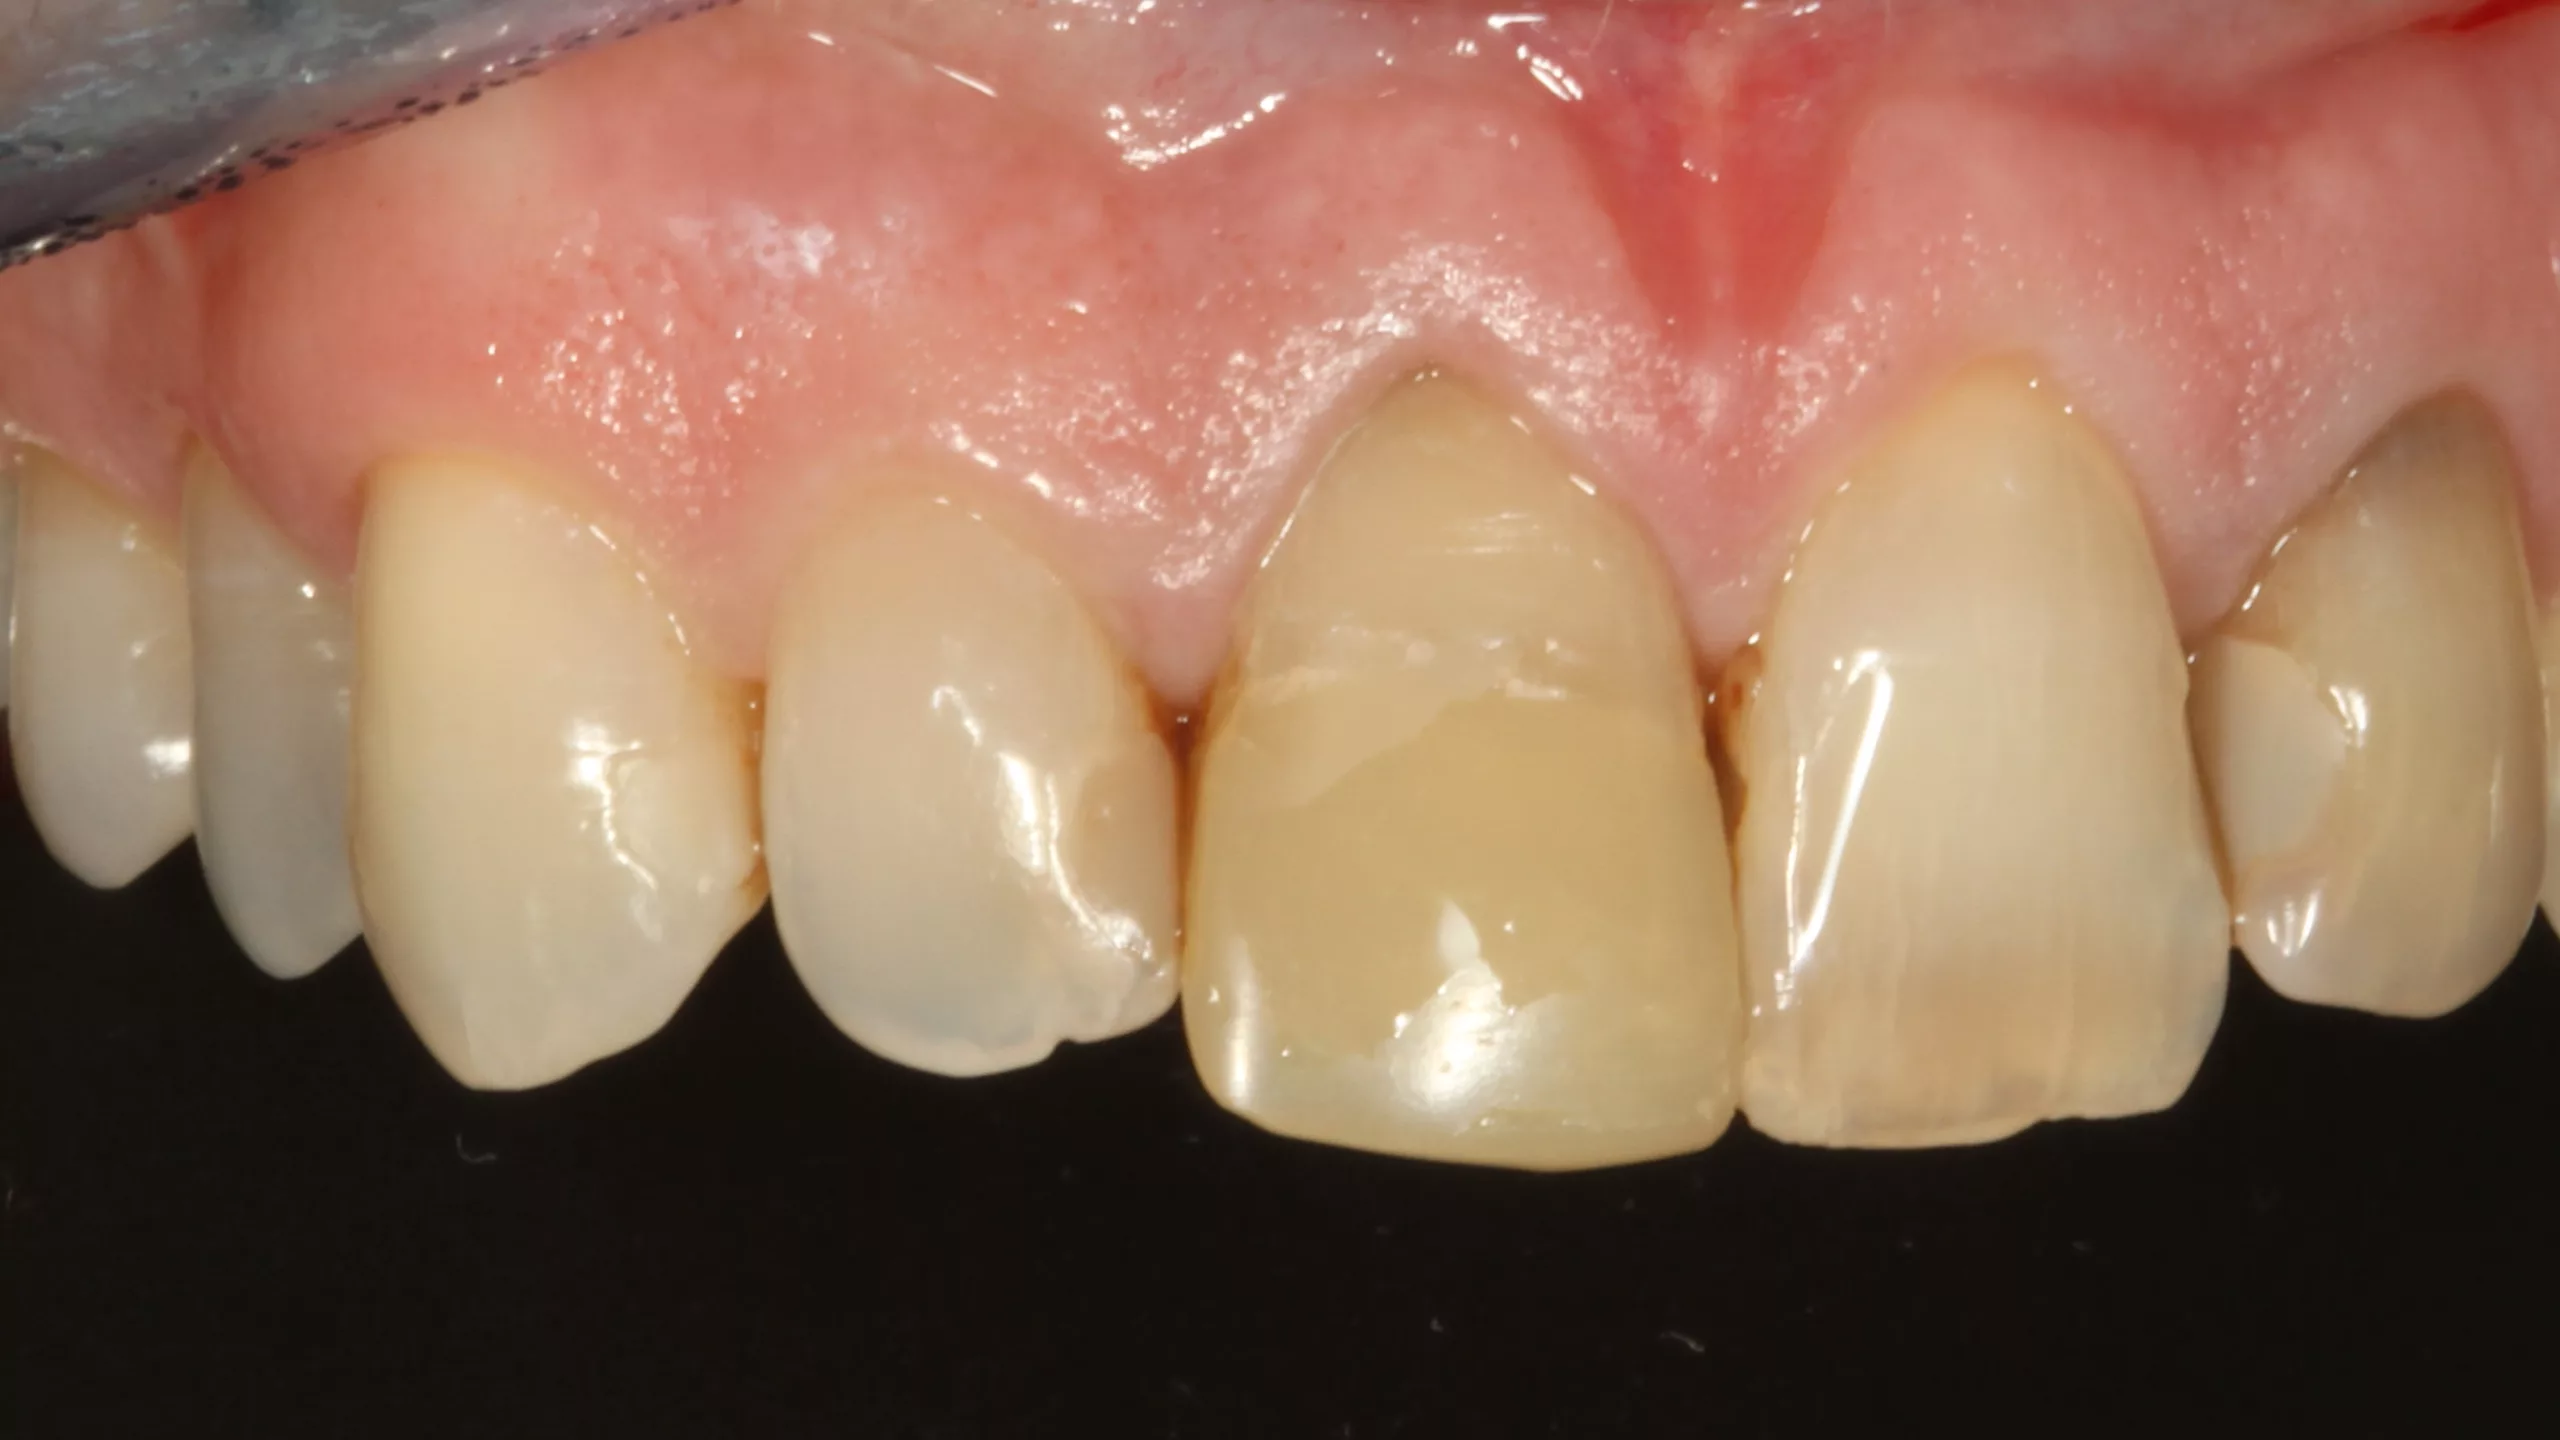

Bei der 55-jährigen Patientin bestand der Wunsch nach einer ästhetischen Neuversorgung ihrer Frontzahnsituation (Abb. 29 und 30). Die Zähne 11 und 22 waren wurzelkanalbehandelt, alle Schneidezähne wiesen ältere, große, farblich nicht mehr passende Kompositversorgungen auf. Die Neuversorgung wurde aufgrund der Stabilität und der besseren Abdeckung verfärbter Zahnbereiche aus einem monolithischen Zirkonmaterial gefertigt, die labial additiv verblendet wurden (Abb. 31 und 32).

Bedingt durch einen Unfall während der Tragezeit des Provisoriums brach das Provisorium an Zahn 11 im inzisalen Drittel samt dem darunter befindlichen, postendodontologischen Kompositaufbau ab. In der Abbildung 33, die die Situation bereits bei der Vorbereitung zur adhäsiven Eingliederung der Gesamtarbeit zeigt, ist der enorme inzisale Substanzverlust gut erkennbar: Erkennbar sind ebenfalls noch Reste des als Aufbaumaterial verwendeten Bulk-Flow-Komposits SDR Flow+ (Dentsply Sirona) in der Farbe U sowie etwas weiß-opaken Venus Diamond Flow Baserliners (Kulzer). Glücklicherweise war der Präparationsrand intakt; die Laborarbeit passte perfekt. Ein Problem bestand nun in der Auswahl des Befestigungsmaterials: Im Prinzip mussten hier gleichzeitig ein Stumpfaufbau und eine adhäsive Befestigung bewerkstelligt werden. Da alle herkömmlichen adhäsiven Befestigungsmaterialien nicht für die Indikation Stumpfaufbau freigegeben sind, schied diese große Gruppe an Befestigungsmaterialien aus. Die Befestigung mit einem adhäsiven Stumpfaufbaumaterial in Form eines „Post & Core“-Konzeptes wäre ein schlechter Kompromiss, da diese Materialien aufgrund ihrer schlechten Polierbarkeit normalerweise nicht dem direkten Kontakt zum Mundmilieu ausgesetzt werden sollten: Erhöhte Plaqueanlagerung oder sogar Verfärbungen am Fügespalt wären ein Risiko, das man ungern eingehen würde.